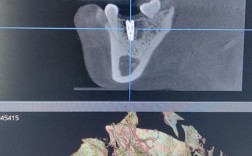

- 术前检查:口腔CT扫描、血液检查等,评估牙槽骨条件。

- CBCT三维影像系统:精准评估骨量